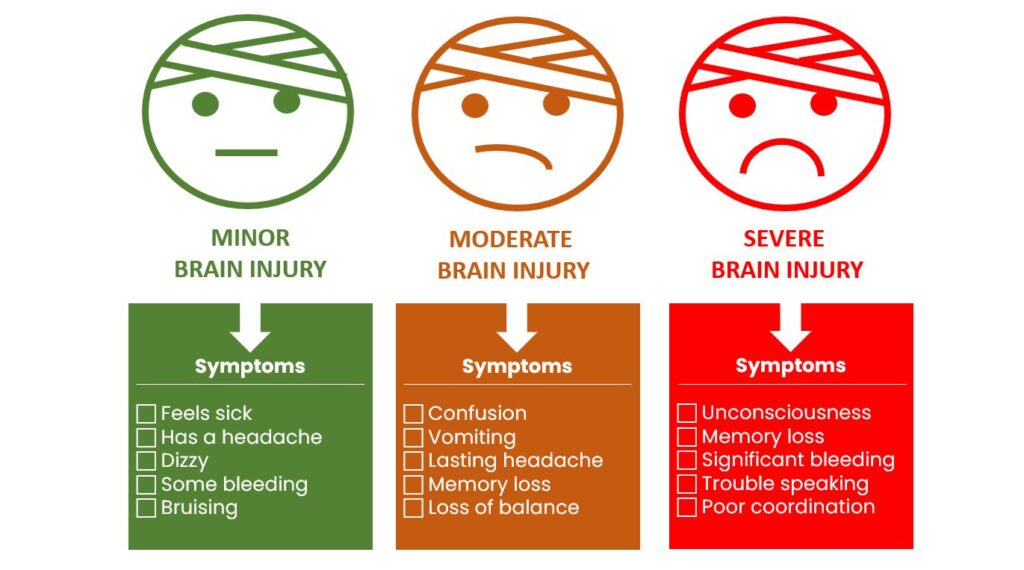

Different tests done in the hospital will help to know how big the brain injury may be.

The more serious the injury, the longer your special person will likely stay in hospital.